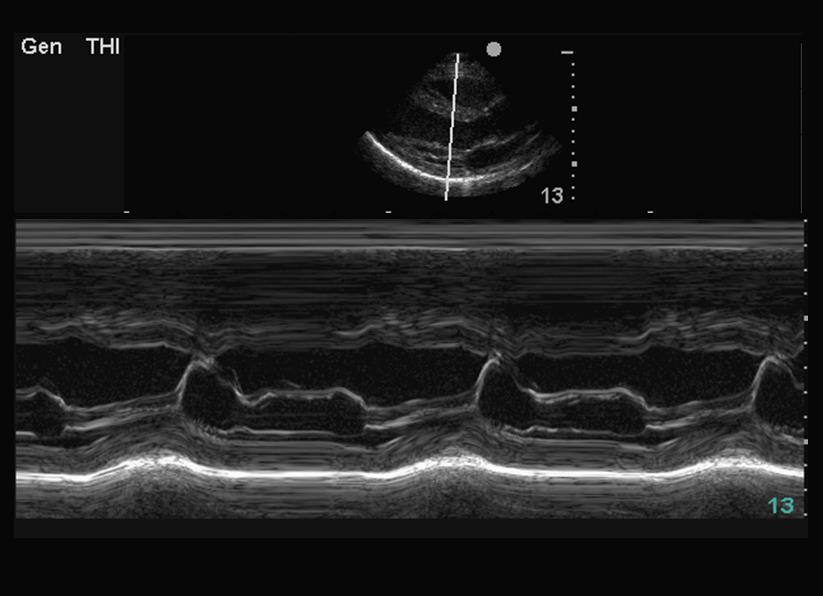

M-Mode/Motion Mode Image